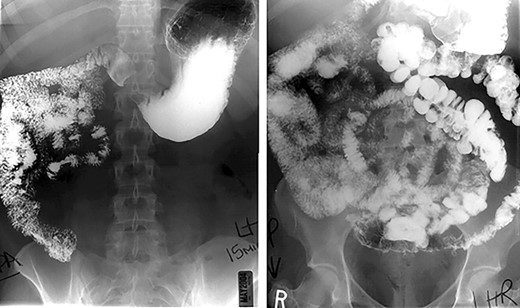

The operative course went as follows for those patients with IM discovered preoperatively: first, primary access to the peritoneal cavity was established with a 12 mm optical trocar placed approximately 4 cm to the left of the midline, 15 cm inferior to the xyphoid process. Second, a 5 mm port was placed in the epigastrium for liver retraction. Third, remaining ports (Fig. 2b) were slightly shifted to the right of our standard positions by 3–4 cm: 5 and 12 mm ports were placed in the right upper quadrant for the surgeon to complete the supramesocolic portion of the procedure. Fourth, 5 and 12 mm ports were placed in the left upper quadrant for the surgeon to complete the inframesocolic portion of the procedure. The first assistant used the ports opposite to the surgeon. Fifth, using these port positions, the surgeon can typically complete the upper abdominal portion of the operation from the patient’s right side and the lower abdominal portion of the operation from the patient’s left side. On the occasion that the orientation of the gastrojejunostomy does not provide adequate access for stapler placement or suturing from the patient’s right side, the surgeon can complete the anastomosis from the patient’s left. Sixth, a 15 ml gastric pouch was completed from the patient’s right side. Inspection of the lower abdomen confirmed the diagnosis of midgut non-rotation. The pylorus was identified and multiple Ladd’s bands were encountered. The entire small intestine was found in the right abdomen. With no rotation, the cecum is typically found in the midline of the lower abdomen and the majority of the remaining colon was often obscured by omentum. Seventh, the jejunojejunostomy was constructed using a ‘mirror image’ approach with the surgeon working from the patient’s left side. Our approach was to add 20 cm to our standard biliopancreatic limb length to account for mobility of the proximal small intestine related to the absence of the ligament of Treitz. Following division of Ladd’s bands, the pylorus is identified, and the jejunum transected 80 cm distal. A 100 cm Roux limb is right-oriented with a right-sided biliopancreatic limb and an antiperistaltic jejunojejunostomy. The anastomosis was constructed using a linear-stapler technique with sutured enterostomy closure; the mesenteric defect was closed with a running non-absorbable suture. The Roux limb was passed in an antegastric, paracolic fashion to allow construction of the gastrojejunostomy. The anastomosis was completed using the same technique as the jejunonejunostomy (Fig. 3). This was completed from the left side of the patient.

Port placement during laparoscopic Roux-en Y gastric bypass in setting of malrotation anatomical variant, standard port sites (a) and modified port sites (b).

In order to optimally manage these difficult cases, besides a thorough knowledge of the possible anatomic abnormalities, a standardized intraoperative approach is paramount. Our intraoperative approach to midgut non-rotation or malrotation follows a standard pattern with technical considerations related to port placement, identification or confirmation of a midgut rotational anomaly, lysis of Ladd’s bands, construction of the Roux limb, gastrojejunal anastomosis and management of the appendix and gallbladder. If IM is identified preoperatively, our routine gastric bypass ports are shifted rightward, ~3–4 cm to improve operative angles and the left upper quadrant 5 mm port is replaced with a 12-mm port.